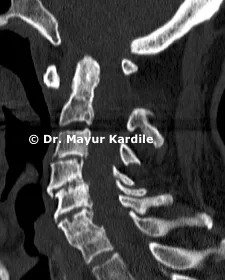

ACDF for Cervical Radiculopathy

61 yr gentleman